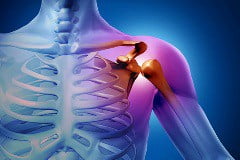

Остеосаркома. Наиболее часто встречающийся вид рака костей, который затрагивает кости верхних и нижних конечностей, и кости таза. Опухоль начинает развиваться в клетках костной ткани. Обычно встречается у детей и молодых людей до 30 лет. Иногда диагностируется у людей 60-70 лет. Данная опухоль чаще встречается у мужчин, чем у женщин.

Гигантоклеточная опухоль кости. Данный вид рака костей чаще встречается в области коленного сустава. Иногда опухоль поражает кости конечностей. Встречается у больных среднего и пожилого возраста. Опасна гигантоклеточная опухоль тем, что при каждом повторном рецидиве стремится захватить близлежащие органы и ткани.

При дальнейшем развитии заболевания появляются следующие симптомы — деформация участка тела в области опухоли или контуров пораженной конечности, часто развивается отек мягких тканей. При пальпации можно обнаружить ткань новообразования, которая обычно неподвижна относительно близлежащих мягких тканей. Нередко опухоль очень болезненна, кожа над ней горячая, что объясняется развитием воспалительного процесса. Объективные признаки рака костей появляются через 2-3 месяца после появления боли. Сначала рост опухоли достаточно быстрый, но затем он может замедлиться или вообще прекратиться. Определяемая при пальпации опухоль указывает на распространение опухолевого процесса в близлежащие мягкие ткани. Кожа, которая покрывает опухоль большого размера, утончается, становится бледной с заметным рисунком расширенных вен. Такие опухоли редко прорастают в кожу.